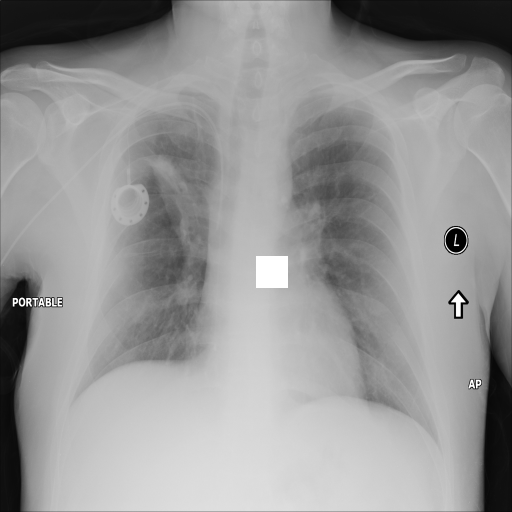

7.2 Qualitative assessment of LDP-processed CXR images

Here, we assume two possible privacy leakage scenarios. To CXR images, we intentionally add features that can lead to the re-identification of the subject appearing in a CXR image. The first feature is an artificial block marker. The second feature is a rare anatomical abnormality known as situs inversus simulated by flipping a CXR image along the vertical axis. Figs. 3(a) and 3(c) show CXR images with the artificial block marker. Fig. 5(a) shows a flipped CXR image to represent a case of situs inversus. We applied DP-GLOW to these CXR images. In Figs. 3(b) and 3(d), the image domain LDP fails to obfuscate the artificial block marker with a moderate privacy budget. In contrast, in Figs. 4(b) and 4(d), DP-GLOW successfully obfuscated the artificial block marker with the moderate privacy budget. On the other hand, the anatomical shape of the chest and the abnormal opacity (hilar regions in the case 1) are preserved. In Fig. 5(b), we observed that the right edge of the heart does not become obfuscated with the image domain LDP. In contrast, in Fig. 6(b), we observed that the right edge of the heart becomes obfuscated and the heart appears at the center of the thoracic cage with DP-GLOW. However, DP-GLOW with this privacy budget is insufficient to almost completely erase the feature of situs inversus.